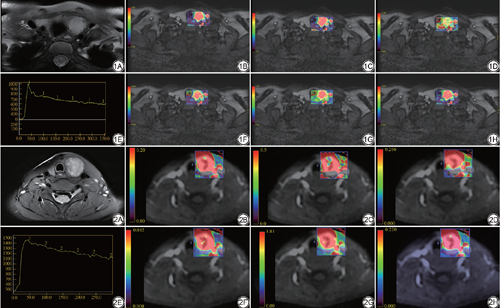

图像分析在GE (AW Volume Share 7)后处理工作站,使用 Functool中的 Gen IQ及Ready view软件包分别进行图像后处理。所有的参数ROI由2名主治及以上放射科医生分别进行勾画,获取定量、半定量参数以及时间-信号曲线(time-intensity curves,TIC)类型(图1,2),具体步骤如下。

以T2WI作为参考图像,在动态增强图像上选取信号异常的最大层面画一个ROI,避免囊变、钙化、出血等区域;基于药代动力学模型计算出定量参数:容积转运常数(Ktrans)、速率常数(Kep)、血管外细胞外容积分数(Ve),单位均为min-1。

在增强图像上选取强化最明显的一层画ROI,得到半定量参数包括:(1)增强曲线下初始面积(initial area under the gadolinium curve,IAUGC),即注射对比剂开始90 s内TIC下面积;(2)最大增强斜率Max Slope=最大[Cti+1-Cti]/(ti+1-ti),其中C为对比剂浓度,ti为增强开始的时间点,ti+1为强化最明显的时间点;(3)对比增强比率(contrast enhancement rate,CER)=(增强后峰值信号强化-基线信号强度)/基线信号强度。

将图像导入GE后处理工作站中Ready view软件包进行,在结节强化最明显的地方进行勾画得到动态增强时间-信号曲线(time-intensity curves,TIC),曲线的横坐标代表时间,纵坐标代表信号强度,根据曲线形态可分为3种类型:Ⅰ型缓慢上升型(整个扫描过程中信号持续上升);Ⅱ型速升平台型(早期信号达峰后,至约增强中晚期时降低幅度<10%);Ⅲ型速升流出型(早期信号强度达峰后,至约增强中晚期时降低幅度>10%)。